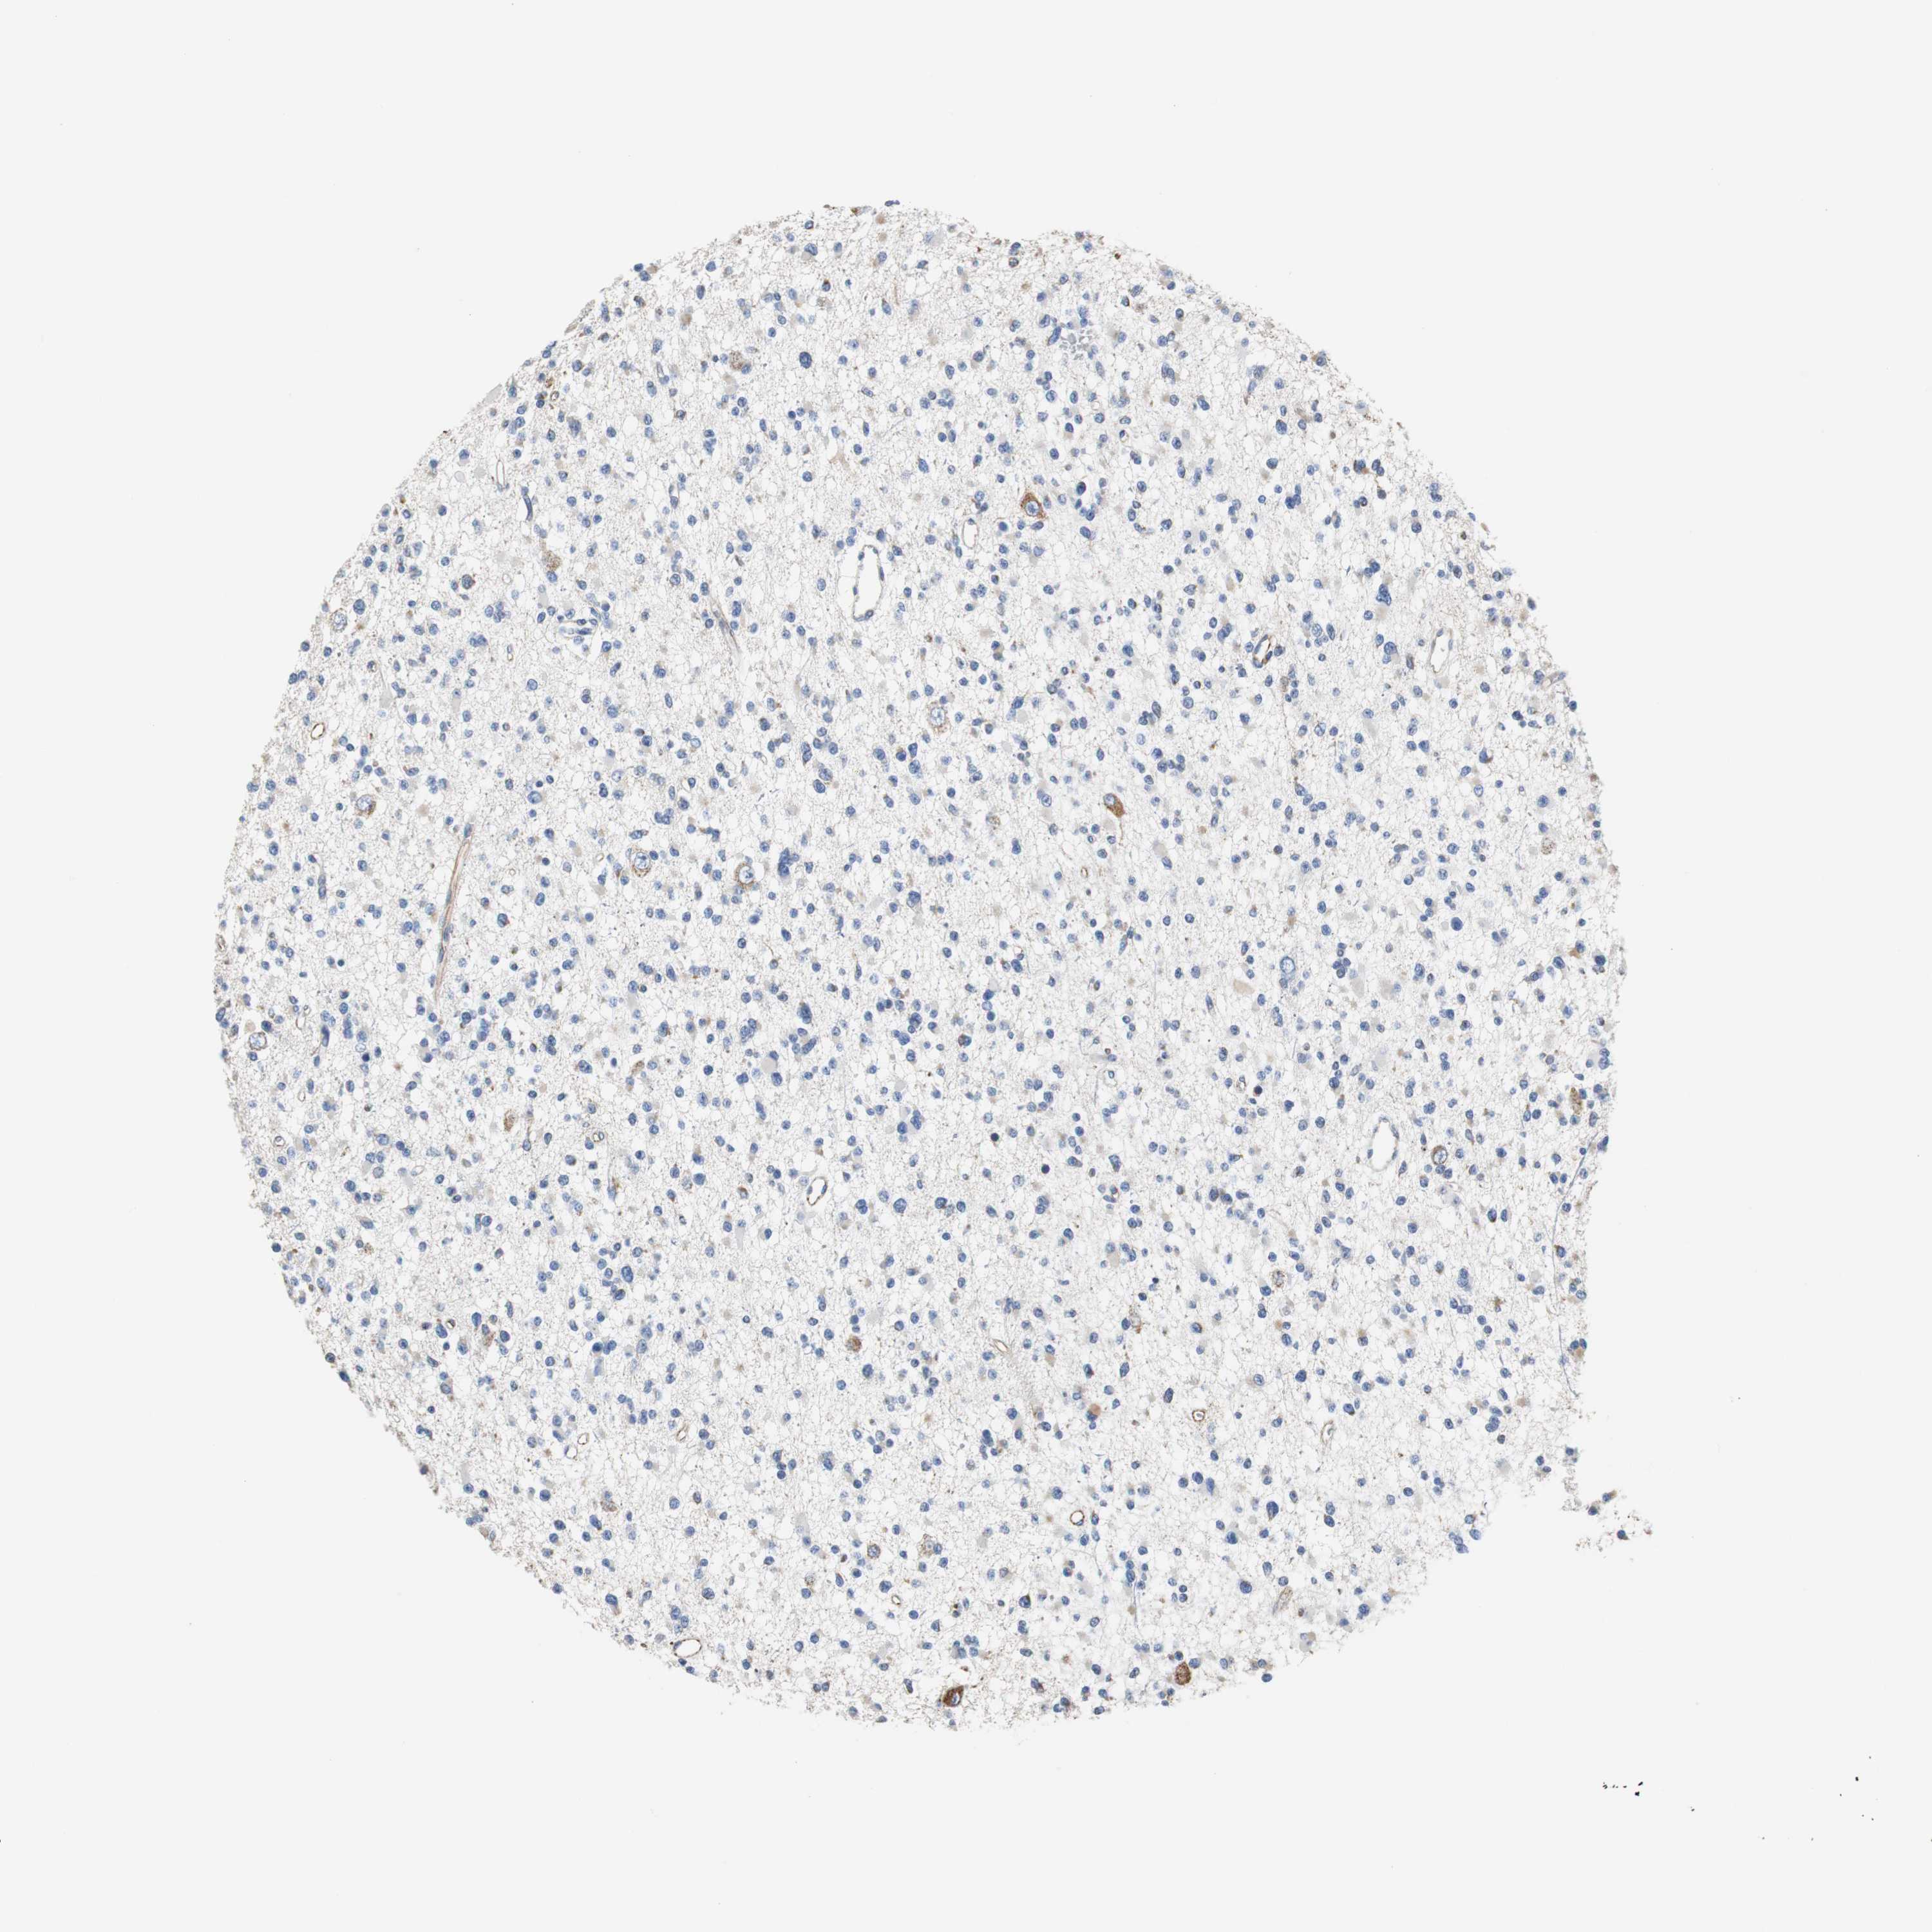

GLIOMA - Protein expressioni

A mouse-over function shows sample information and annotation data. Click on an image to view it in a full screen mode. Samples can be filtered based on level of antibody staining by selecting one or several of the following categories: high, medium, low and not detected. The assay and annotation is described here.

Note that samples used for immunohistochemistry by the Human Protein Atlas do not correspond to samples in the TCGA dataset.

Antibody stainingi

Antibody staining in the annotated cell types in the current human tissue is reported as not detected, low, medium, or high, based on conventional immunohistochemistry profiling in selected tissues. This score is based on the combination of the staining intensity and fraction of stained cells.

Each image is clickable and will lead to virtual microscopy that enables deeper exploration of all samples and also displays staining intensity scores, fraction scores and subcellular localization as well as patient and tissue information for each sample.

Antibody HPA006277

Antibody HPA006507

Antibody CAB017027

Staining

High

Medium

Low

Not detected

Intensity

Strong

Moderate

Weak

Negative

Quantity

>75%

75%-25%

<25%

None

Location

Nuclear

Cytoplasmic/membranous

Cytoplasmic/membranous,nuclear

Glioma, malignant, Low grade

Glioma, malignant, High grade